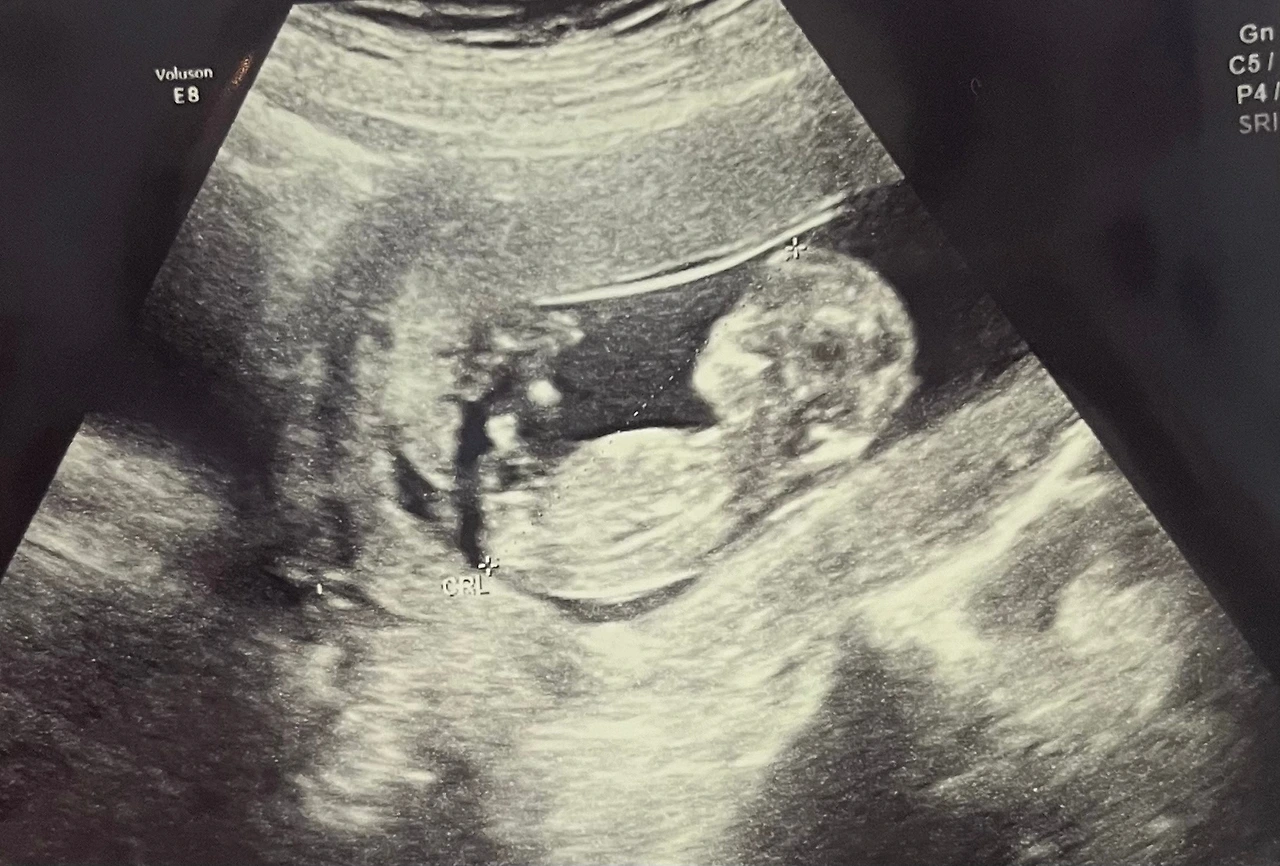

검사는 생각보다 간단했다. 산모의 채혈을 뽑는 것과 초음파를 보는 것 두 가지뿐이었다. 피검사 결과는 다음 정기검사에 같이 이야기를 해준다고 했고, 초음파는 평소 의사 선생님 진료실에서 보던 것과는 달리 정밀초음파실에서 입체초음파로 자세히 봤다. 평소보다 오래 봤는데, 이 시기에 의료진이 확인해야 하는 부분이 있는 것 같다. 목투명대, 코뼈, 몸길이, 양팔, 양다리, 손가락, 발가락 등 외형적으로 봤을 때 이상이 없는지를 봤다. 이때 화면 속으로 너무 귀여운 아이에게 감동받으면서도 동시에 의료진의 입에서 예상치 못한 말이 나오진 않을까 하는 걱정이 동시에 들었다.

초음파실에서 너무 활발하게 움직여서 사진 찍는데 애먹었단다.

'만세!'하고 있는 모습에 검사하면서 다 같이 빵 터졌어.